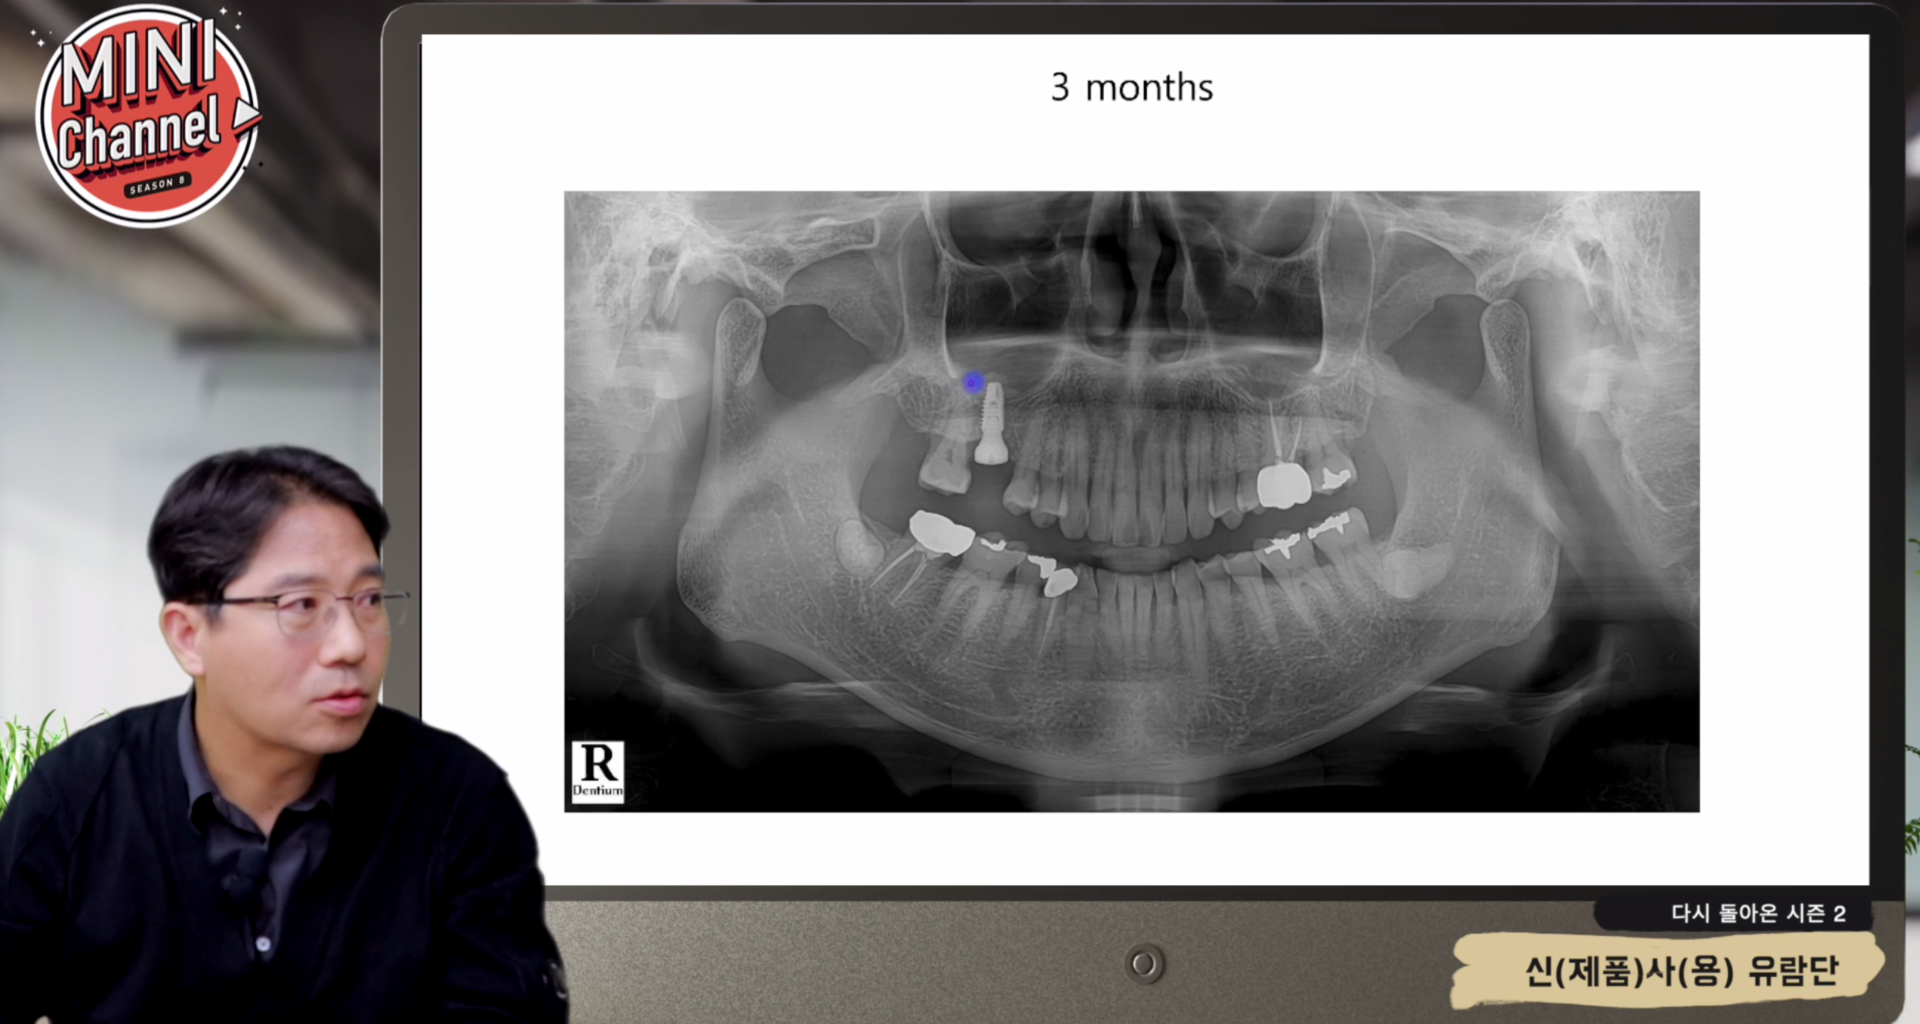

SES KIT 증례에서는 잔존골이 충분치 않은 케이스에서도 크레스타 접근으로 즉시 식립 + 동시거상을 반복해서 보여준다. 수술 직후 파노라마/CT와 3개월·6개월 추적 영상에서 dome 형태가 크게 변형되지 않고 유지되는 것이 인상적이다.

단순히 "막을 안 찢었다"가 아니라, 골과 이식재가 섞이면서 안정적으로 성숙하는 모습까지 데이터를 통해 확인할 수 있다는 점이 이 강의의 큰 장점이다.

SES KIT 동시거상 수술 직후 CT SES KIT 동시거상 추적 CT

▲ 동시거상 직후 vs 추적 CT